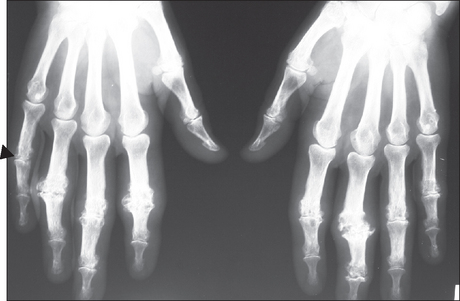

Figure 26.9 Psoriatic arthritis X-ray of the wrist of a patient with psoriatic arthritis; note the ‘pencil in cup’ deformity (tapered proximal osseous surface and expanded base) of the distal bone of the fingers, early ankylosis [arrowhead] of the proximal interphalangeal joint of the right little finger and erosions with proliferative change of the little finger). Note also the lack of osteoporosis.

In mild cases X-rays are normal or show only joint-space narrowing and erosive changes. Unlike the X-rays of rheumatoid joints the bone density is maintained and there may be sclerotic changes in the small bones (see Figure 26.9). Ankylosis of peripheral joints and arthritis mutilans can occur in either condition. The involvement of the spine and sacroiliac joints is asymmetrical, as in Reiter’s syndrome.